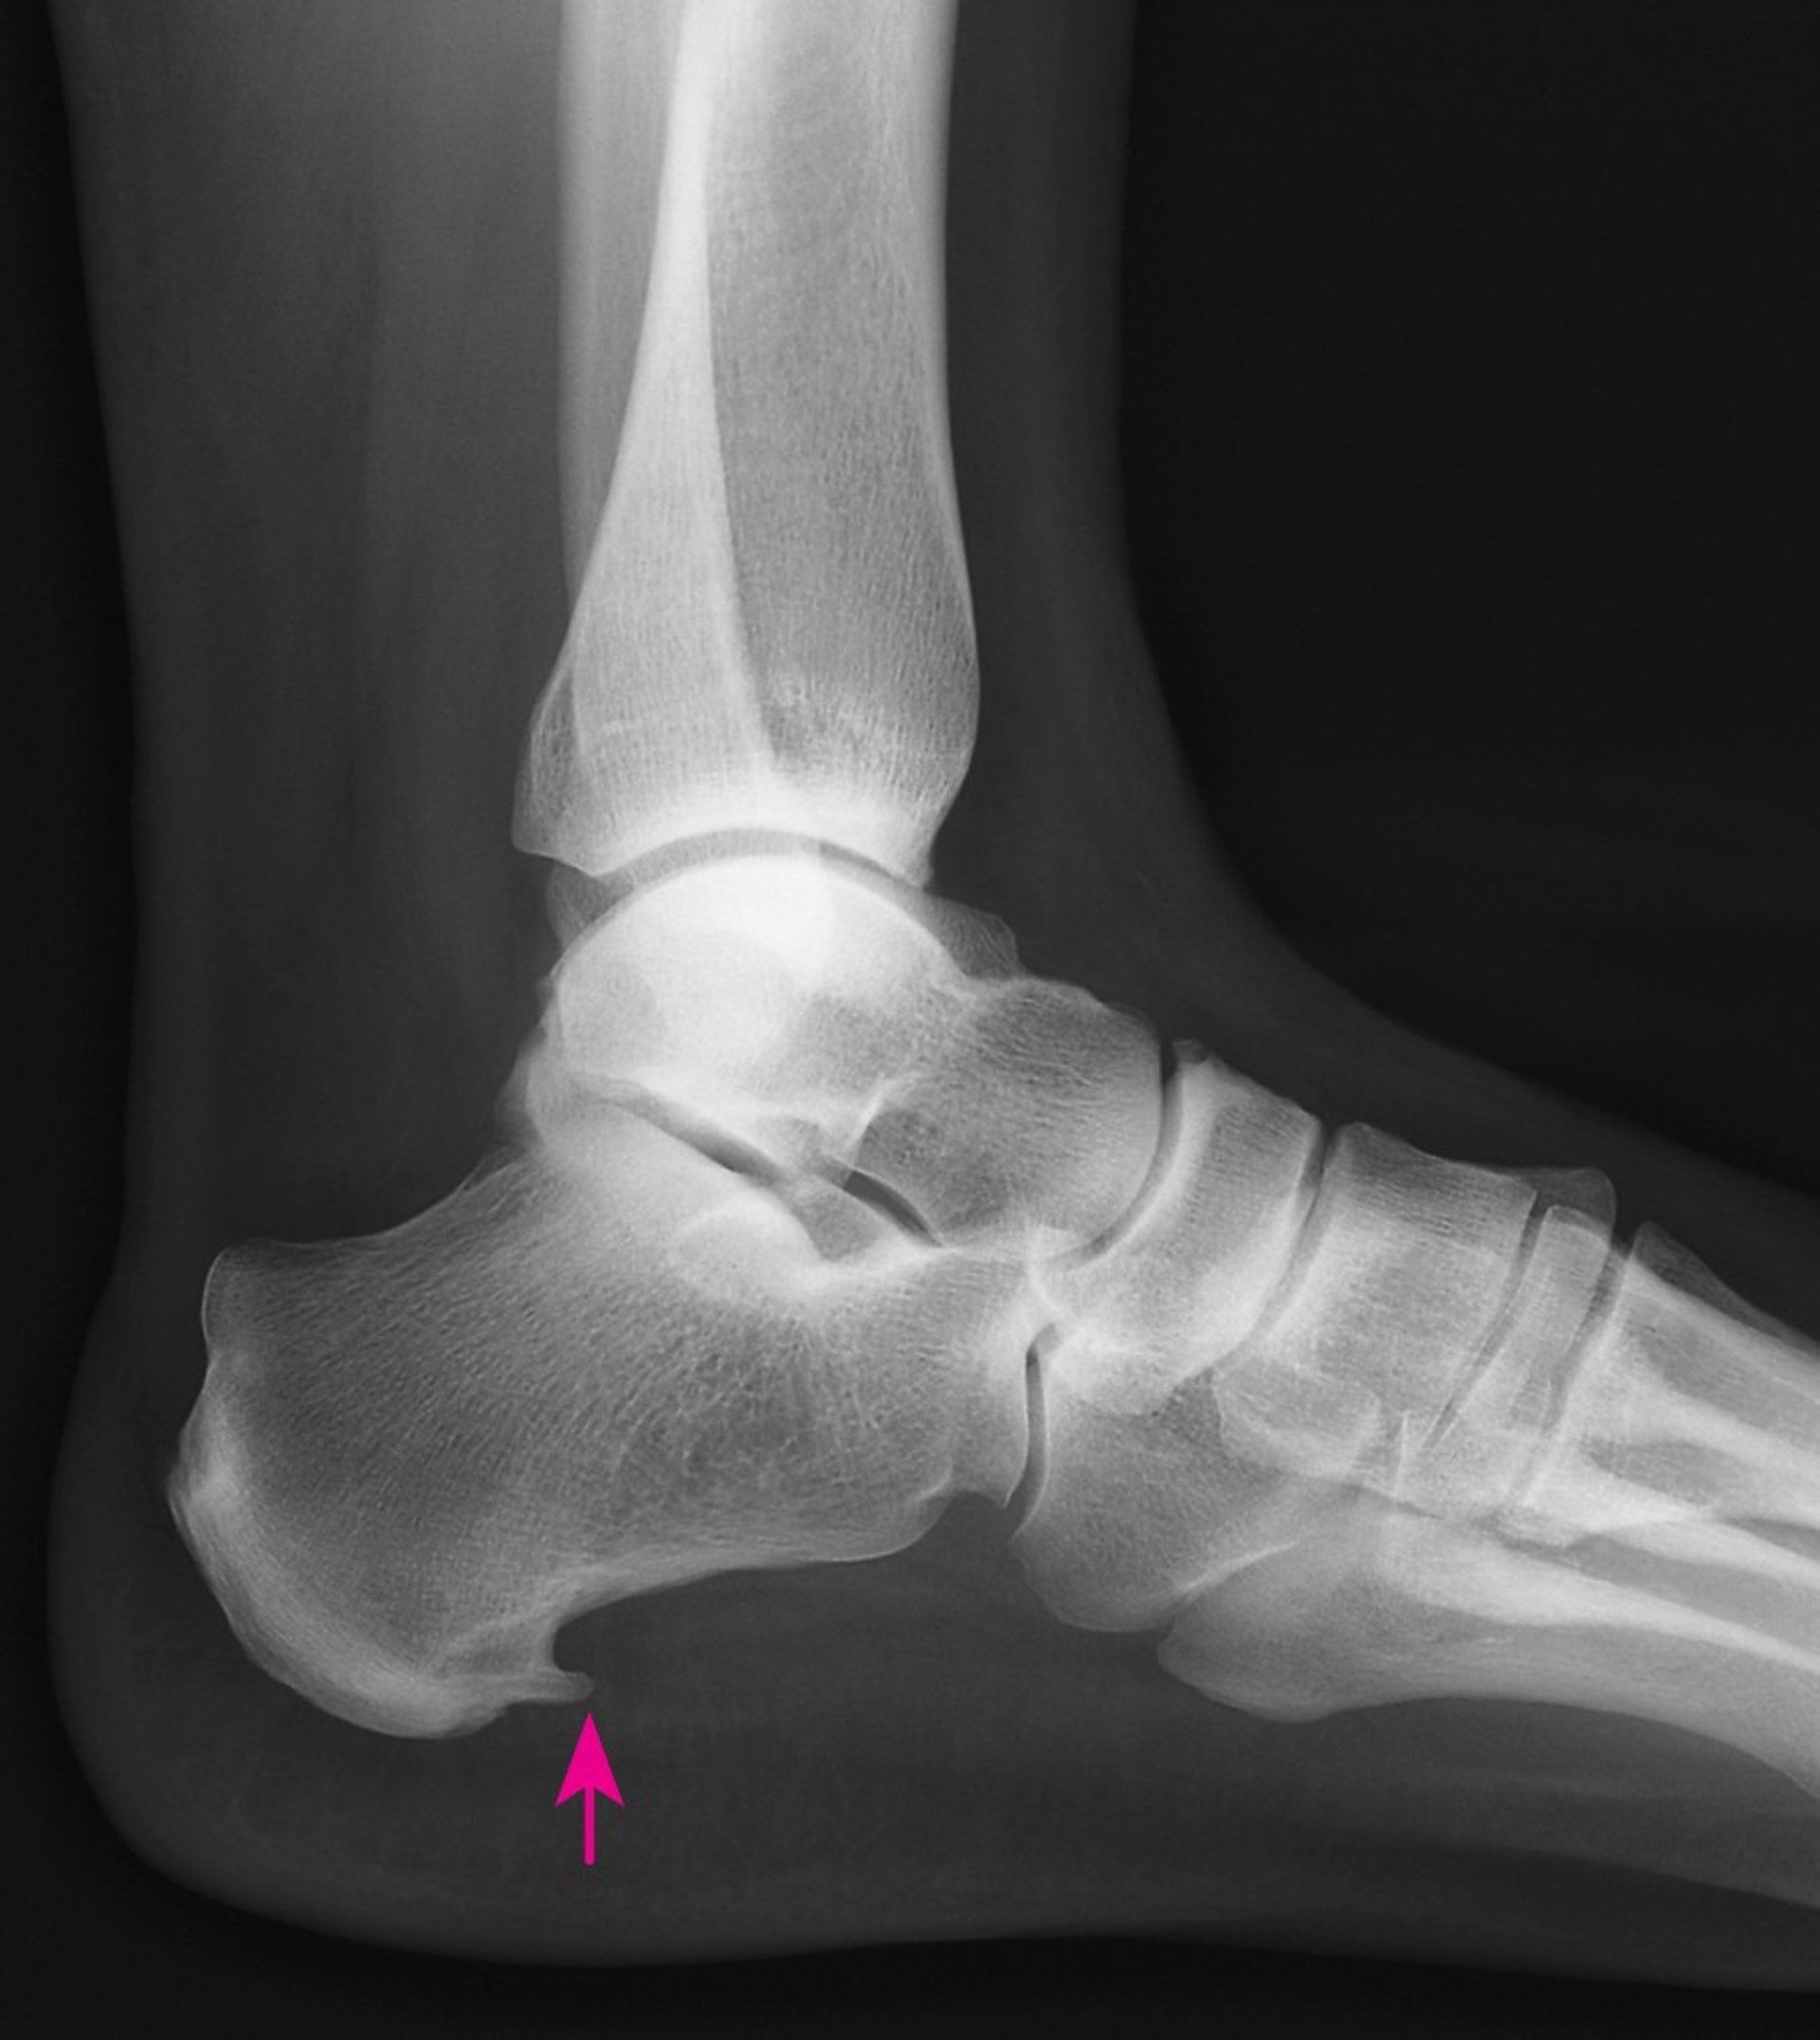

A heel spur is a pointed growth of extra bone on the heel bone (calcaneus). It may form when the plantar fascia, the connective tissue extending from the bottom of the heel bone to the base of the toes (ball of the foot), pulls excessively on the heel. The spur may be painful as it develops but it may become less painful as the foot adjusts to it. Not all heel spurs cause symptoms. When heel spurs do cause symptoms, most can be treated without surgery.

X-rays may show a heel spur protruding from the bottom front edge of the heel bone. However, people with plantar fasciitis often do not have heel spurs, and most people who do have heel spurs do not have pain, so the presence of a heel spur does not necessarily confirm plantar fasciitis and also does not mean the heel spur needs to be treated.